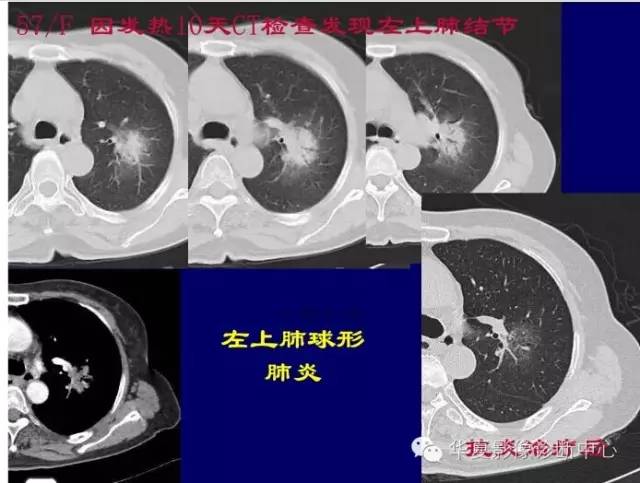

第一步判断是不是肿瘤

孤立性GGO

首先看边缘

是否清楚

GGO的边缘模糊,考虑炎性病变

对于不好定的,不典型的一律建议抗炎后复查

如果不看边缘是否清楚,就好像癌肿

但是一看边缘就是炎性病变

大家记住了,边缘模糊的GGO首先考虑炎症